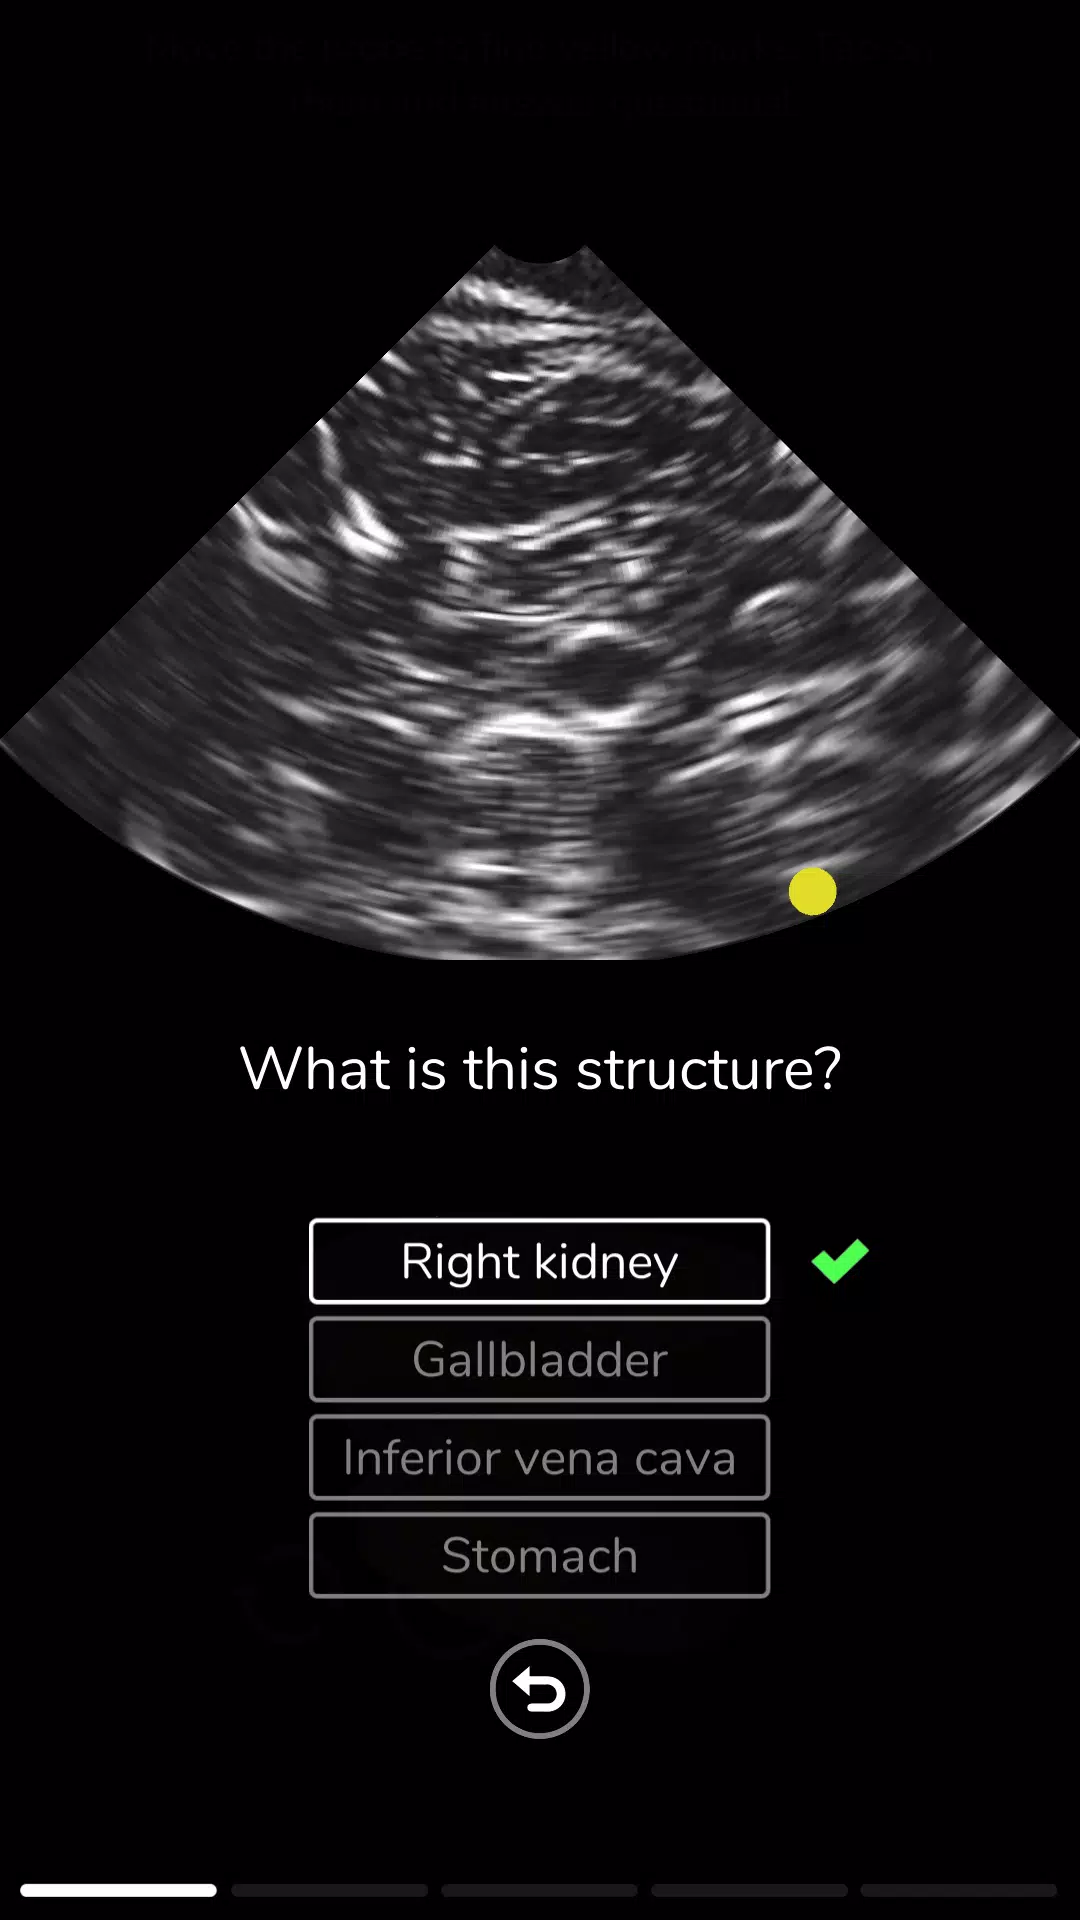

在超声模拟器中学习超声波或超声波扫描技术。 Deepscope超声学习模块由医生和超声医师创建。模块包括: - 基本超声或超声波探头运动 - 与超声扫描检查相关的解剖学 - 进行主动脉超声检查或超声检查的技术 - 进行超声心动图或回声的技术超声模拟器使用先进的计算机图形技术模拟声波。超声波图是作为这些模拟的结果而创建的。该应用程序旨在学习超声波检查或超声波。它可用于急诊医学(ER)超声,手术(术前)超声,骨科超声扫描,风湿病超声检查,血管超声检查,眼科超声和麻醉超声(麻醉学)。对于心脏病学,我们有超声心动图和回声模拟。Deepscope chāoshēng xuéxí mókuài yóu yīshēng hé chāoshēng yīshī chuàngjiàn.Mókuài bāokuò: - Jīběn chāoshēng huò chāoshēngbō tàntóu yùndòng - yǔ chāoshēng sǎomiáo jiǎnchá xiāngguān de jiěpōu xué - jìnxíng zhǔ dòngmài chāoshēng jiǎnchá huò chāoshēng jiǎnchá de jìshù - jìnxíng chāoshēng xīndòng tú huò huíshēng de jìshùchāoshēng mónǐ qì shǐyòng xiānjìn de jìsuànjī túxíng jìshù mónǐ shēngbō. Chāoshēngbō tú shì zuòwéi zhèxiē mónǐ de jiéguǒ ér chuàngjiàn de.Gāi yìngyòng chéngxù zhǐ zài xuéxí chāoshēngbō jiǎnchá huò chāoshēngbō. Tā kěyòng yú jízhěn yīxué (ER) chāoshēng, shǒushù (shù qián) chāoshēng, gǔkē chāoshēng sǎomiáo, fēngshī bìng chāoshēng jiǎnchá, xiěguǎn chāoshēng jiǎnchá, yǎnkē chāoshēng hé mázuì chāoshēng (mázuì xué). Duìyú xīnzàng bìng xué, wǒmen yǒu chāoshēng xīndòng tú hé huíshēng mónǐ. 最新版本2.0更新日志 Last updated on 2023年10月24日 New ModulesNew User Interface